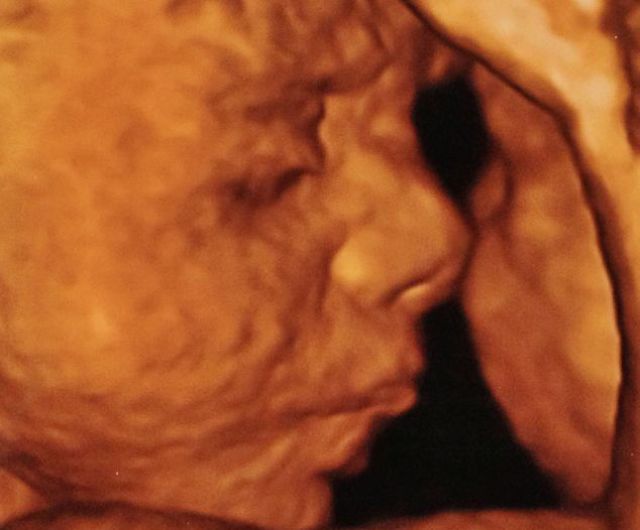

32-week scan